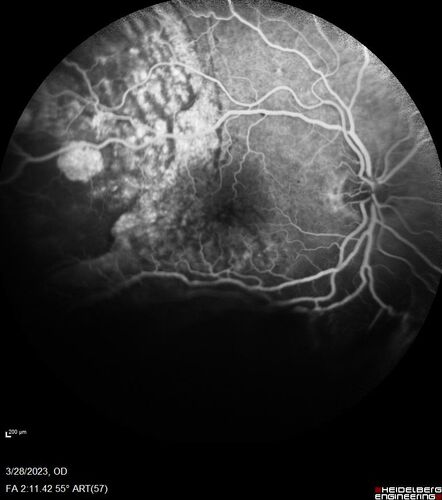

Choroidal Metastatic Breast Cancer with Exudative Detachment

58 year old female presented with 20/200 vision. Had 10 sessions of radiation and tumor shrank. The exudative detachment took almost a year to resolve. The vision improved to 20/40.